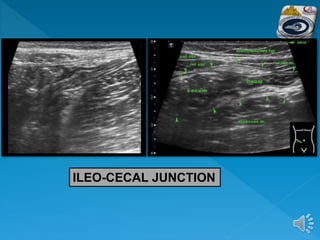

 Beginning at the right anterior superior iliac

spine and moving medially to the edge of the

rectus muscles in a sagittal plane, the right

common iliac vessels are identified.

 Rotating anticlockwise to a transverse plane

and moving cranially, the first bowel loop

crossing from medial to lateral is identified as

the terminal ileum.

 This is followed to the ileocaecal valve and

caecum.

 The base of the appendix can be identified at

the deep margin of the caecum where the three

taenia coli meet

TERMINAL ILEUM

ILEO-CECAL JUNCTION